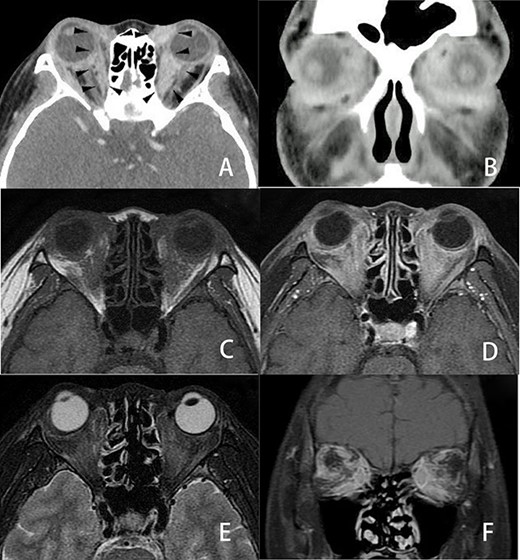

She complained of visual disturbance and bilateral periorbital swelling. An ophthalmological examination revealed limited upturn and abduction movement in the bilateral eyes. Computed tomography (CT) revealed abnormal soft tissue enhancement along the eyeball in the medial to retrobulbar portions of the bilateral orbits (Fig. 2A and B). Magnetic resonance imaging (MRI) (Fig. 2C–F) further indicated an ill-defined mass at the same portion where the soft tissue enhancement had been shown by CT in the bilateral orbits. These orbital tumors were hypointense to fat tissue on T1-weighted imaging but slightly hyperintense to fat tissue on T2-weighted imaging. T1-weighted imaging with contrast showed heterogenous irregular enhancement in the retrobulbar portion of the bilateral orbits. CT and MRI also indicated no destruction of the orbital wall due to bone metastasis. Positron emission tomography indicated a slight uptake in the bilateral orbits, with no significant uptake except for in the bone and orbital space. Since CT and MRI could not differentiate metastatic tumors from inflammatory tumors, such as IgG4-related disease, a trans-palpebral biopsy confirmed the metastasis of ILC (Fig. 1C), which was identical to the primary breast cancer. Thrombocytopenia simultaneously occurred and a biopsy of bone marrow also confirmed metastasis of breast cancer to the bone marrow (Fig. 1E). Immunohistochemical studies demonstrated negative findings for ER (Fig. 1D), PgR and Her2 for orbital metastasis but ER positivity (Fig. 1F) and PgR and Her2 negativity for the bone marrow metastasis.

Three-dimensional imaging findings of orbital metastasis from breast cancer. Axial (A) and coronal (B) CT with contrast showed abnormal soft tissue enhancement (arrow) along the eyeball in the medial to retrobulbar portions of the bilateral orbits. The enhancement of the left orbit was greater than that of the right orbit. Axial MRI (C, D, E) also revealed an ill-defined tumor involving the soft tissues at the same portion where the soft tissue enhancement was seen on CT in the bilateral orbits. These orbital tumors were hypointense to fat tissue on axial T1-weighted imaging (C) and slightly enhanced on axial T1-weighted imaging with contrast (D) but slightly hyperintense to fat tissue on axial fat-suppressed T2-weighted imaging (E). Coronal fat-suppressed T1-weighted imaging with contrast (F) showed heterogenous irregular enhancement in the retrobulbar portion of the bilateral orbits. CT and MRI revealed no destruction of the eyeball, optic nerve or orbital bony wall.